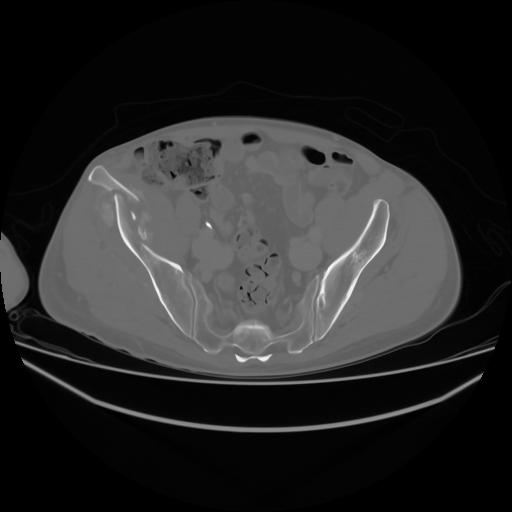

4 CUERPO,CE,Axial,3.0,CUERPO,,